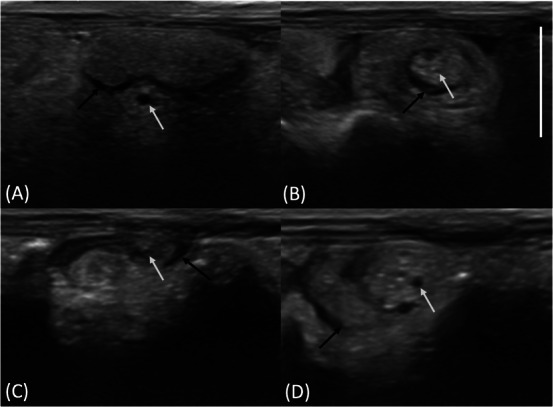

A 6-year-old intact male guinea pig was presented for acute abdominal pain, anorexia, and absence of ambulation for 12 h. Radiographs revealed moderate gastric dilation and multifocal marked small intestinal gas dilation. Ultrasonography showed a focally dilated jejunal loop with abrupt narrowing and torsion, with a mesenteric vascular "whirl sign". The aborad jejunum was empty. Surgery revealed a focal mesenteric torsion with associated segmental jejunal torsion and consequent jejunal occlusion. A cardiopulmonary arrest occurred during the surgery. This is the first report of diagnostic imaging findings associated with mesenteric torsion in a guinea pig.